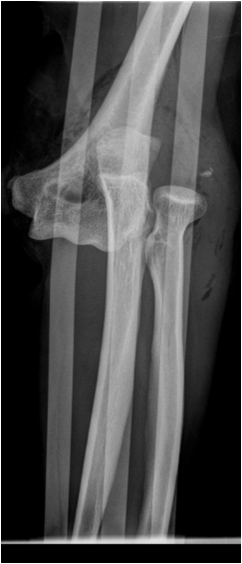

Fig. 11. Growth plate fracture with involvement of metaphysis and epiphyis (Salter-Harris type IV.